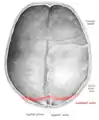

Lambdoid suture

Lambdoid suture (labeled at bottom right)

The lambdoid suture (or lambdoidal suture) is a dense, fibrous connective tissue joint on the posterior aspect of the skull that connects the parietal bones with the occipital bone. It is continuous with the occipitomastoid suture.

The lambdoid suture is between the paired parietal bones and the occipital bone of the skull. It runs from the asterion on each side.

The lambdoid suture is named due to its uppercase lambda-like shape.